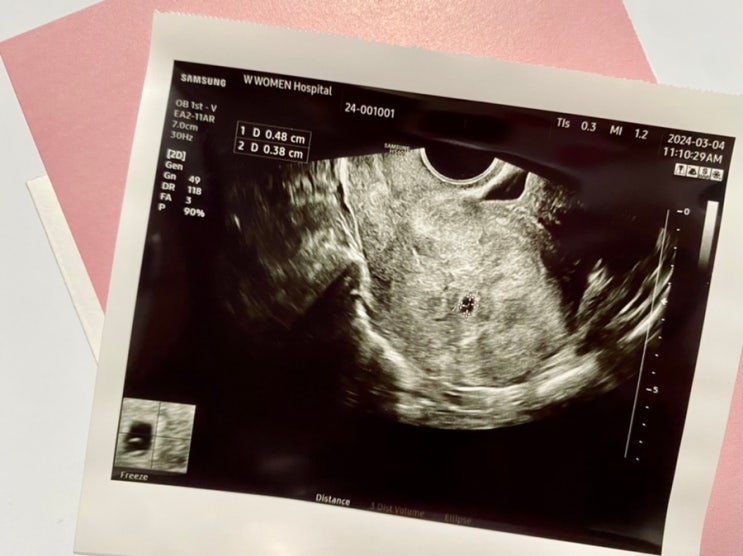

첫임신, 7주차 자연유산 자연배출/ 어떤 기억은 아파도 오래 간직하고 싶기에

*결혼 3년차 그동안 일부러 피임을 한적은 없지만, 그렇다고 임신을 위해 애쓴적도 없었다. 사실 생리주기...